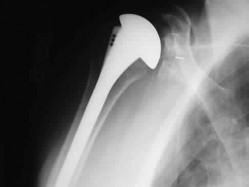

A 72-year-old female undergoes a reverse total shoulder arthroplasty (rTSA) for severe rotator cuff tear arthropathy. Compared to the native anatomic shoulder, which of the following best describes the biomechanical alteration of the center of rotation following a standard Grammont-style rTSA?

Explanation

The classic Grammont-style reverse total shoulder arthroplasty relies on a medialized and inferiorized (distalized) center of rotation. This biomechanical alteration increases the tension and moment arm of the deltoid muscle, which compensates for the deficient rotator cuff to allow active forward elevation.